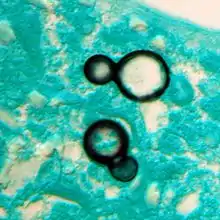

Once suspected, the diagnosis of blastomycosis can usually be confirmed by demonstration of the characteristic broad based budding organisms in sputum or tissues by KOH prep, cytology, or histology.[16] Tissue biopsy of skin or other organs may be required in order to diagnose extra-pulmonary disease. Blastomycosis is histologically associated with granulomatous nodules. Commercially available urine antigen testing appears to be quite sensitive in suggesting the diagnosis in cases where the organism is not readily detected. While culture of the organism remains the definitive diagnostic standard, its slow growing nature can lead to delays in treatment of up to several weeks. However, sometimes blood and sputum cultures may not detect blastomycosis.[17]

Granuloma with early suppuration. Fungal organisms difficult to recognize at this low magnification.

Large yeast-like fungi seen within giant cells at arrows.

Large yeast-like fungi seen within giant cells at arrows.Budding yeasts in cytoplasm of giant cells at arrows. Broad-based budding and double contoured cell wall seen in the giant cell in the center is characteristic of Blastomyces dermatitidis.